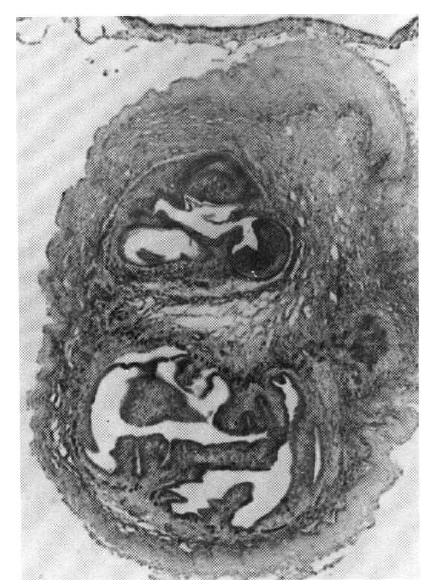

A biopsy of a subcutaneous nodule was done on the 4th hospital day, and upon microscopic examination, a bladder worm (Fig. 5)—its hooks (Fig. 6) and parenchymatous portion with spinal canal and separated bladder of the cysticercus (Fig. 7)—was observed. On the 12 th hospital day, the presence of cysticercus was confirmed by an open lung biopsy (Fig. 8).

Cross section of C. cellulosae shows the fully differentiated parenchymatous portion and the still separated bladder of the cysticercus.